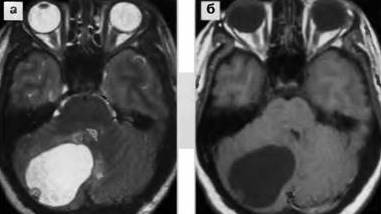

Доброкачественная опухоль мозга, по мнению врачей, представляет собой образование, которое не проникает в окружающие ткани и не метастазирует. Обычно такие опухоли имеют четкие границы и медленно растут. Врачи отмечают, что симптомы могут варьироваться в зависимости от локализации опухоли, но часто включают головные боли, изменения в зрении, слухе или координации. На МРТ доброкачественные опухоли выглядят как яркие участки с четкими контурами, что позволяет легко их отличить от злокачественных образований. Важно отметить, что даже доброкачественные опухоли могут вызывать серьезные проблемы, если они оказывают давление на жизненно важные структуры мозга. Поэтому регулярные обследования и консультации со специалистами крайне важны для своевременной диагностики и лечения.

Как выглядит доброкачественная опухоль на МРТ?

Доброкачественная опухоль на МРТ. Однородная структура. Четкие, ровные контуры. Отсутствие перифокального отека. Слабое по сравнению со злокачественной опухолью накопление контрастного вещества (менее яркая).